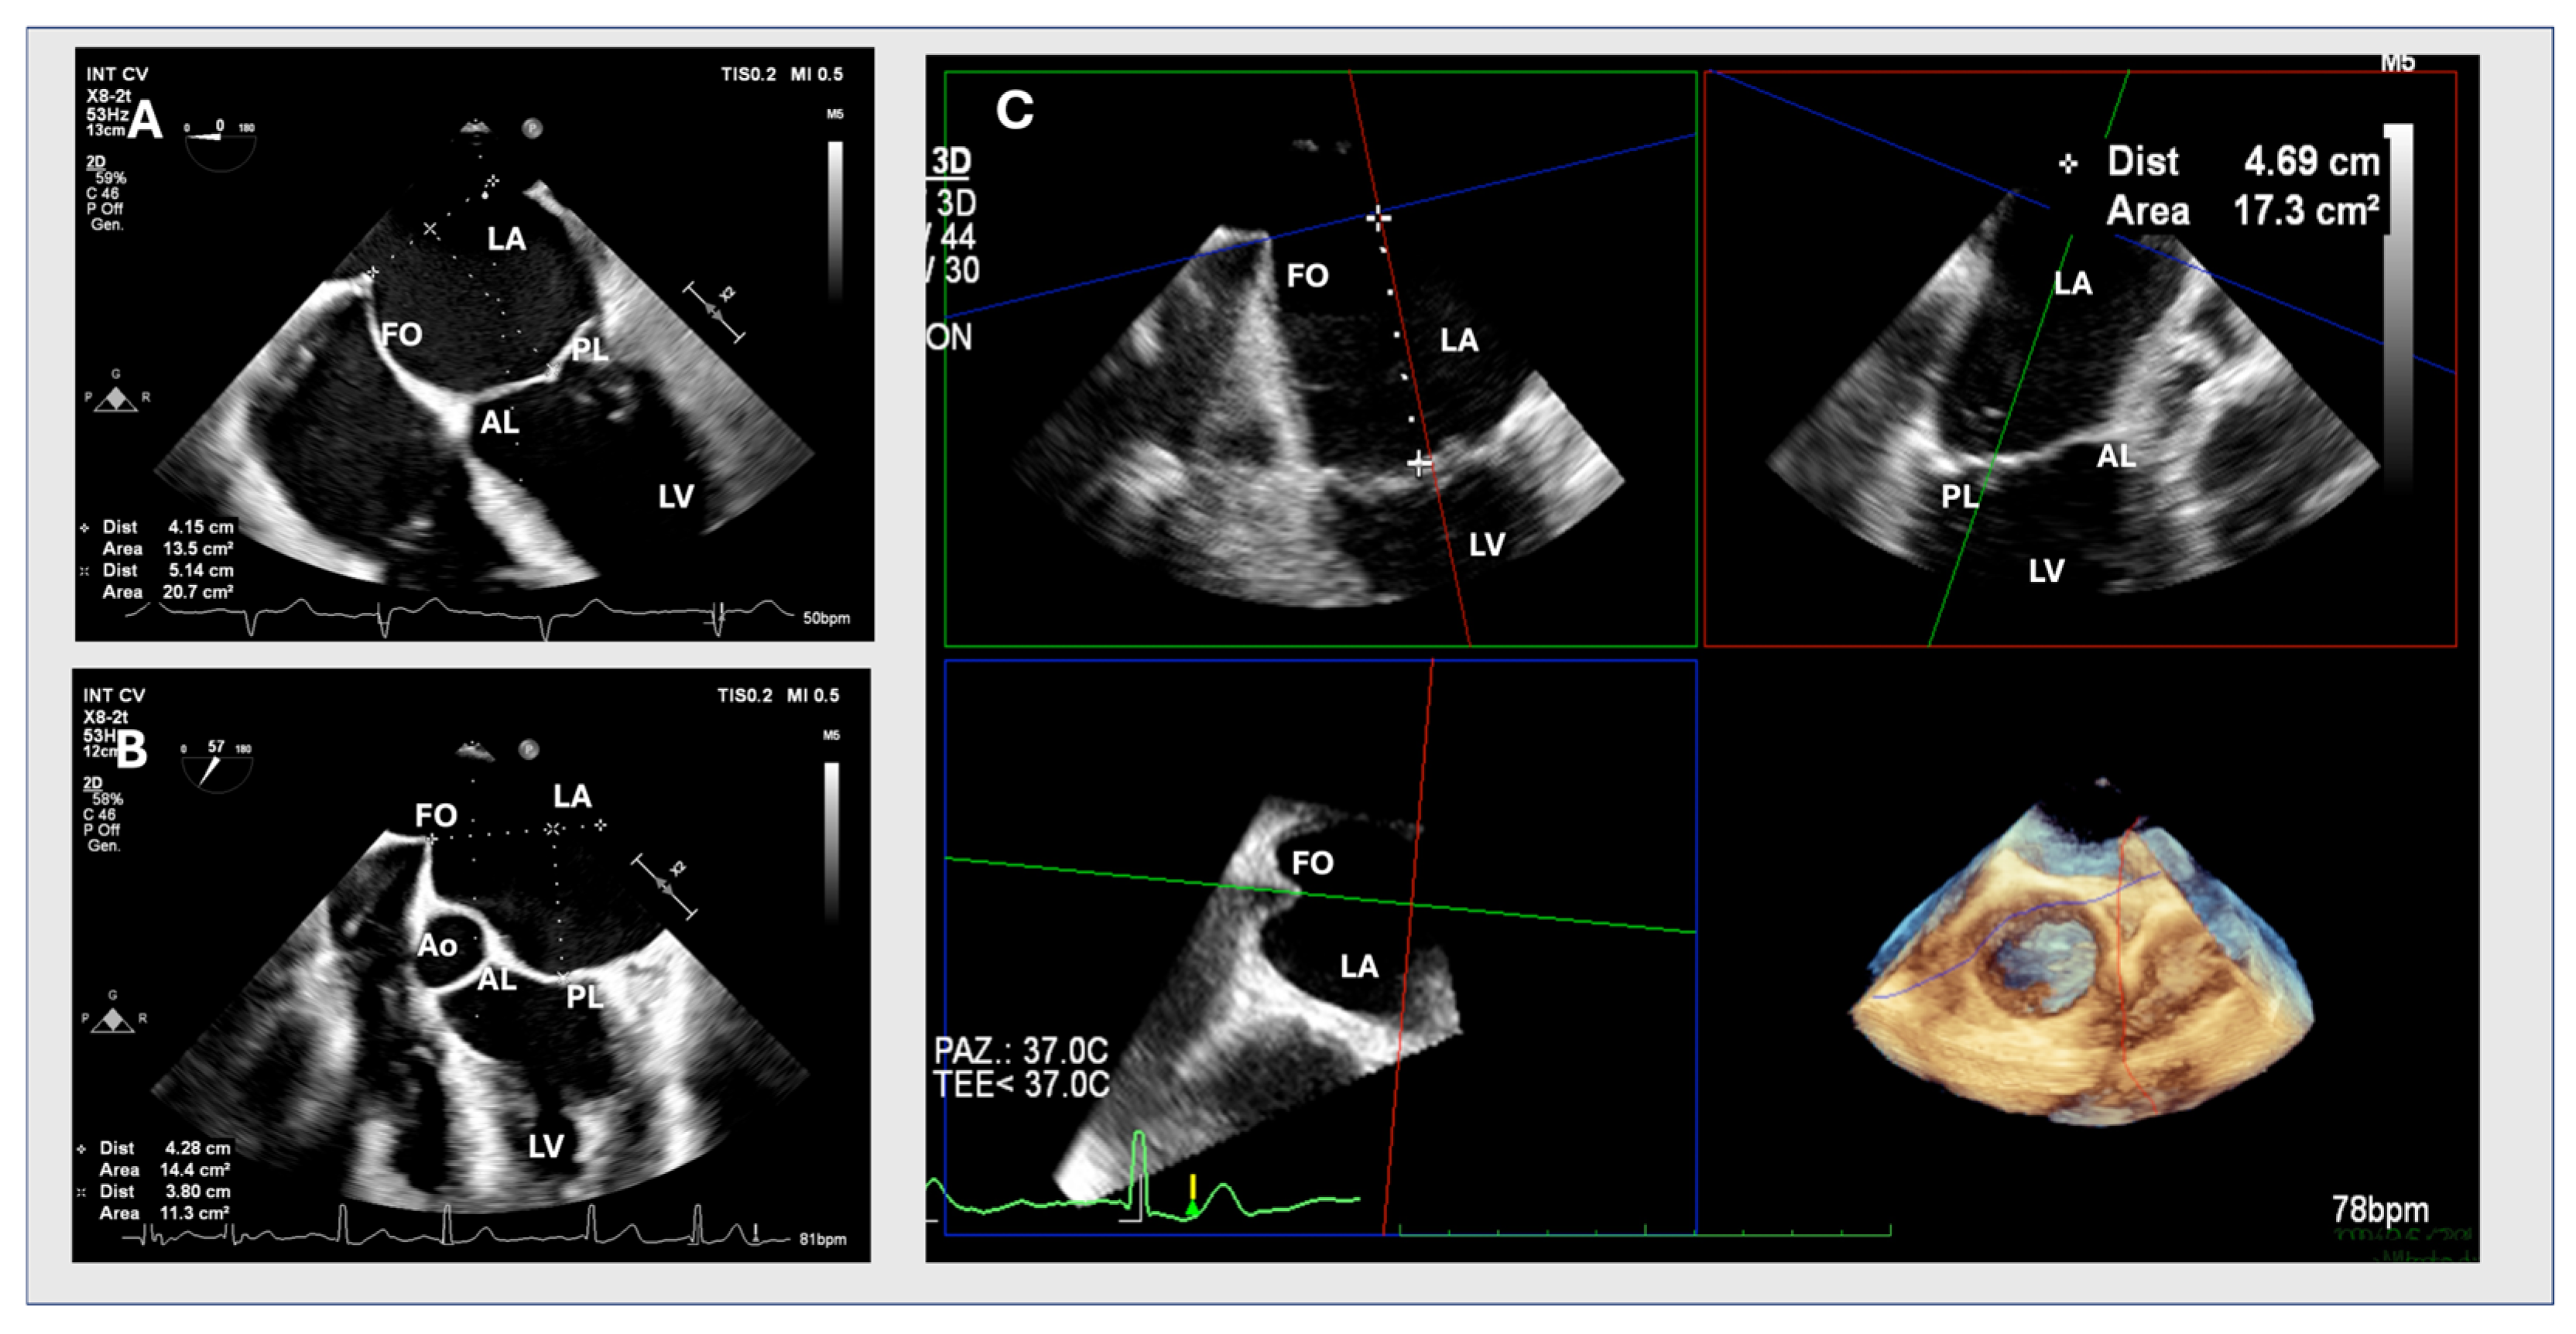

1. Introduction

2. Materials and Methods

2.1. Two-Dimensional Method

2.2. MPR Method